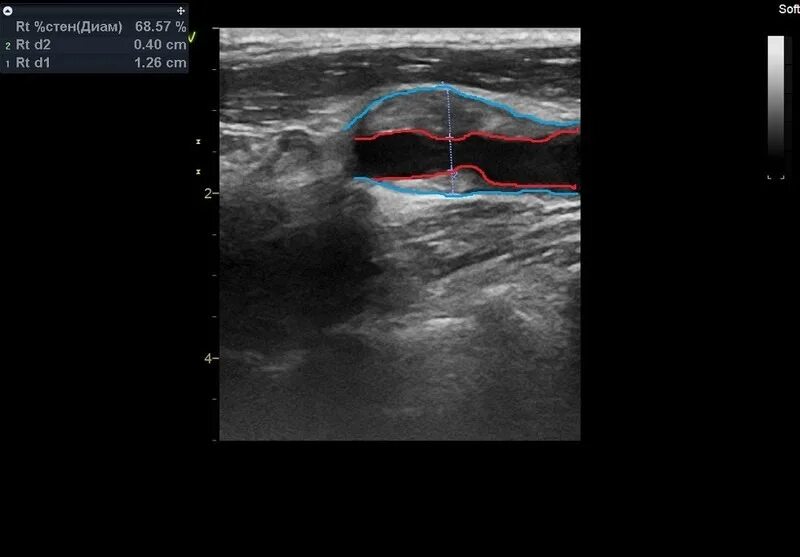

Сделать узи сонной артерии